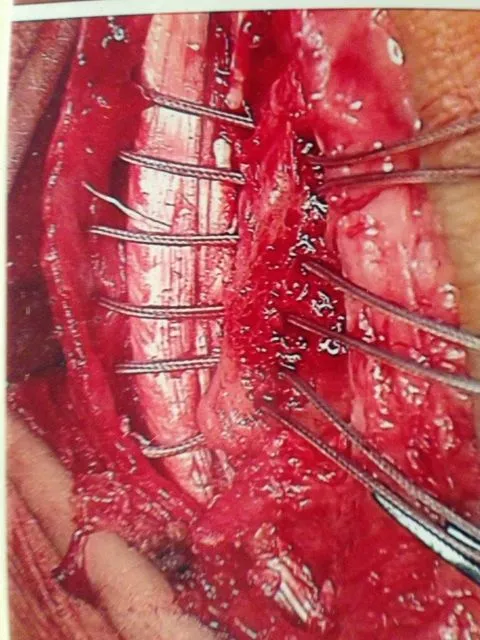

Pics of repair of peroneal retinaculum for dislocating peroneal tendons

The sutures can be seen prior to repair

The retinaculum is repaired through drill holes in the fibula and the sutures are woven through the bone

Pic after complete repair